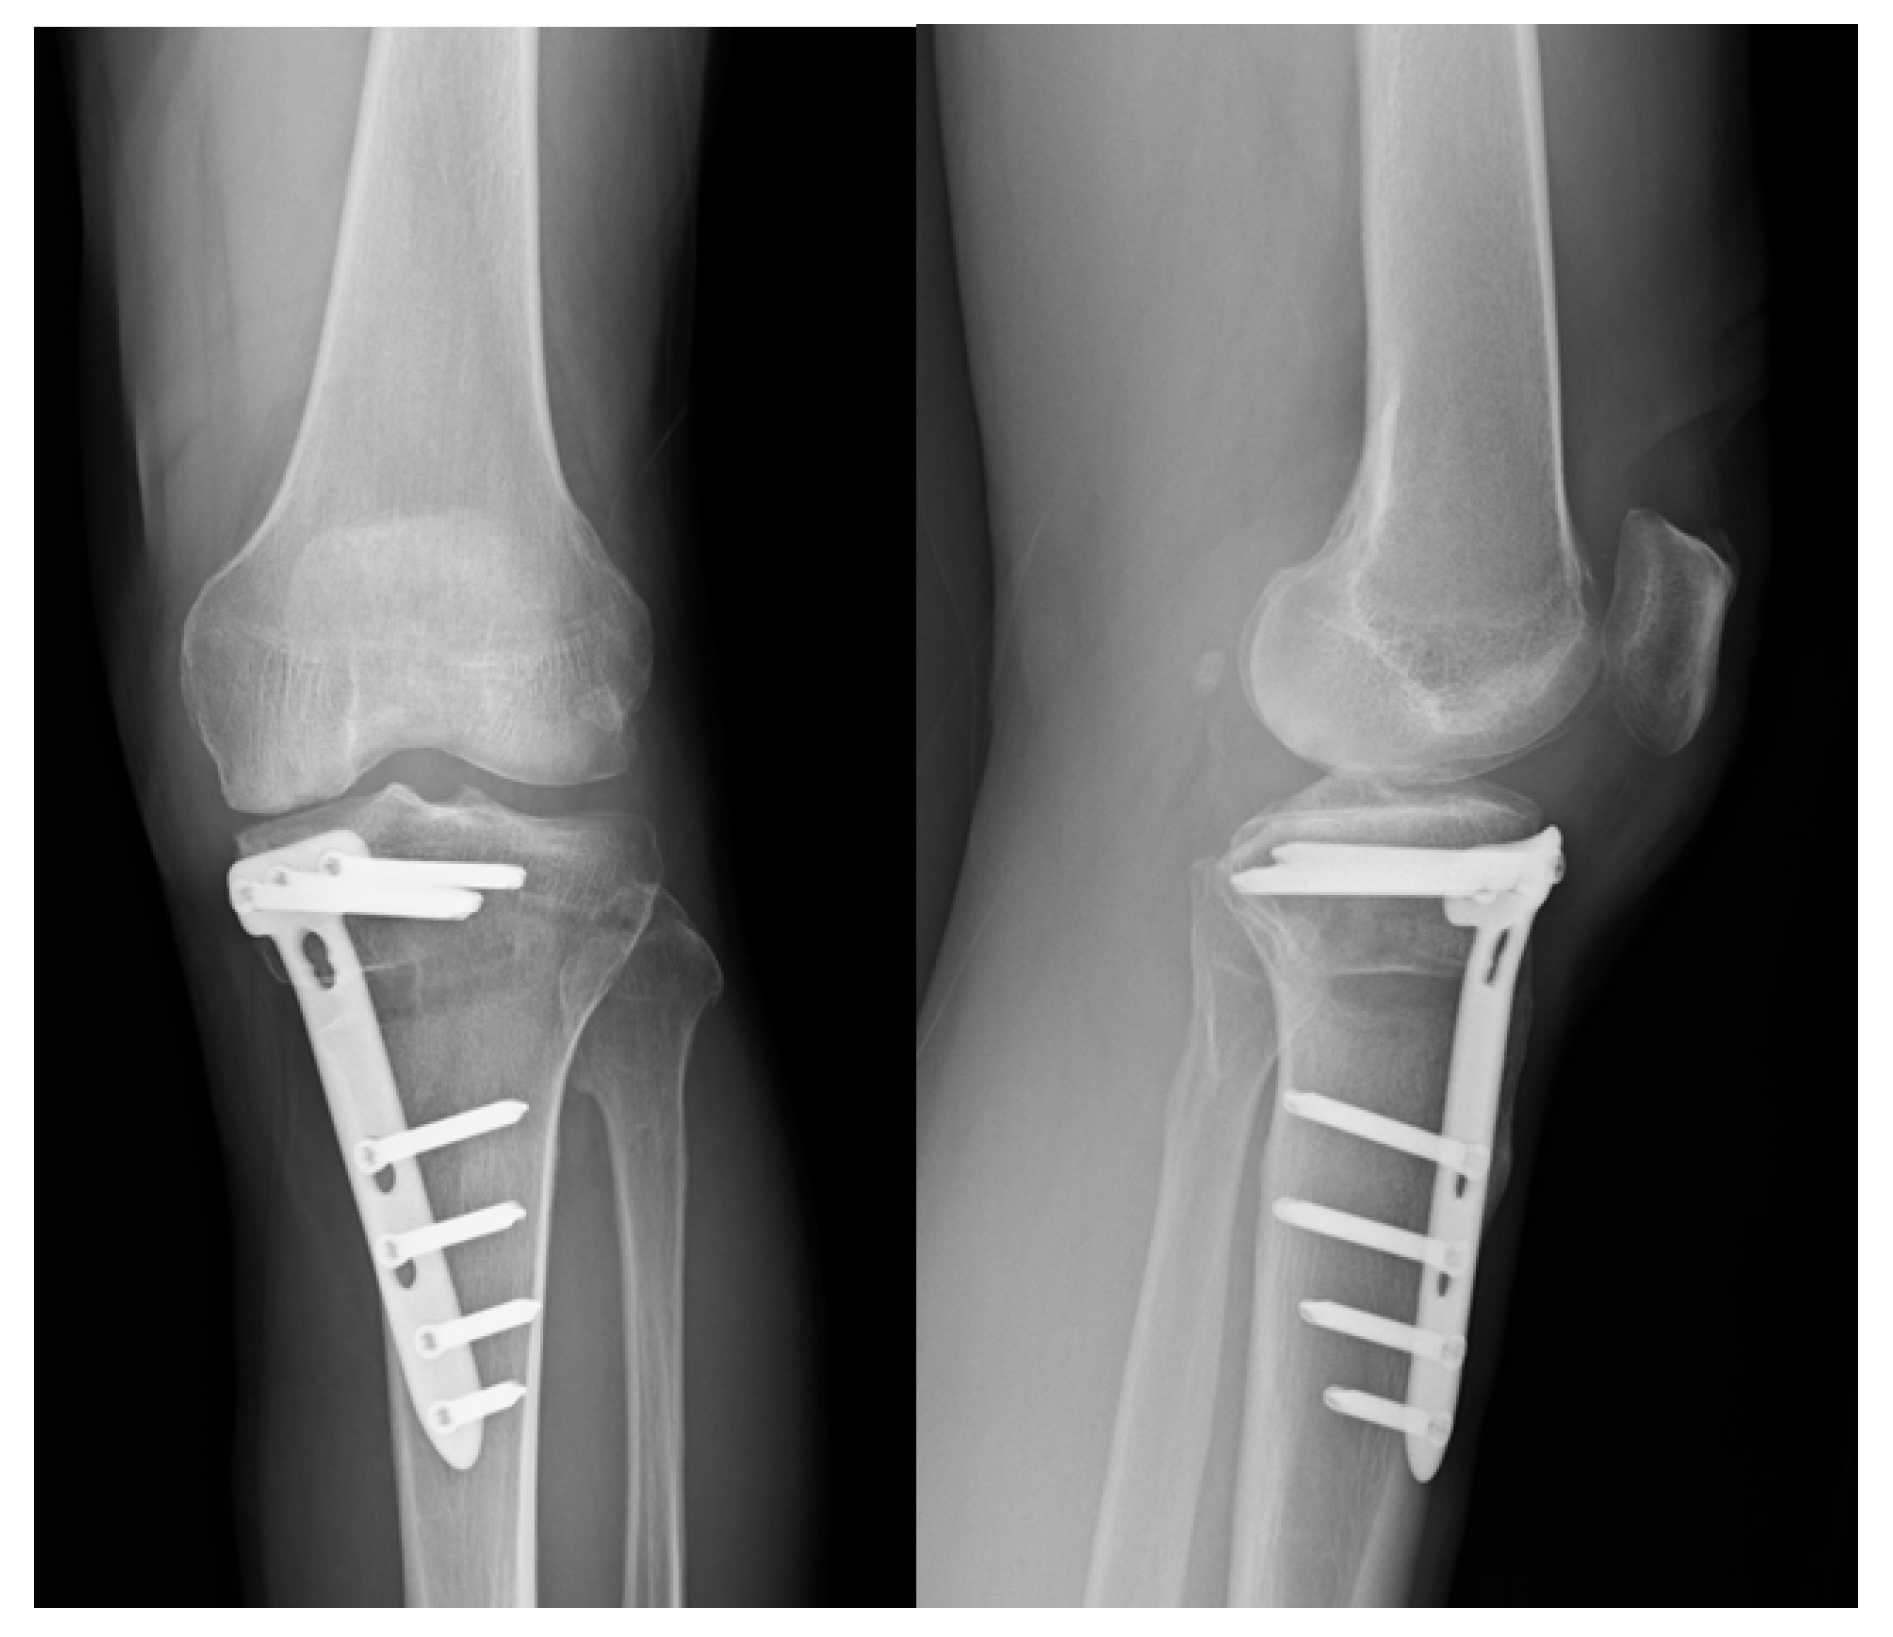

| M, 64, 25.3 | HCV | yes | 17 degree | nil | 3 months | No growth | Arthroscopic debride of knee joint, open debride of osteotomy site tics with daptomycin and Ceftazidime for a total of 6 weeks | 8 months |

| M, 58, 26.1 | Type II DM | yes | 9 degree | nil | 2 weeks | Staphylococcus epidermidis | Arthroscopic debride of knee joint, open debride of osteotomy site, systemic antibiotics with daptomycin for total of 6 weeks | 8 months |

| M, 46, 26.4 | Nil | yes | 11 degree | Lateral hinge fracture, Takeuchi type III, fixation with cannulated screws × 2 | 2 months | MSSA | Open debride of osteotomy site, systemic antibiotics with Oxaxillin for a total of 6 weeks | 8 months |